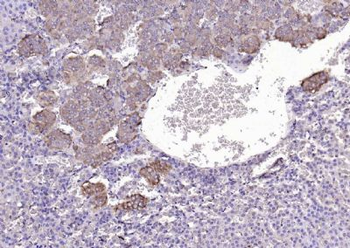

100 μl, 200 μl, 50 μlGoat anti-CYP26B1 Antibody [orb19329]

ELISA, FC, IHC

Canine, Human, Mouse, Rat

Goat

Polyclonal

Unconjugated

100 μg